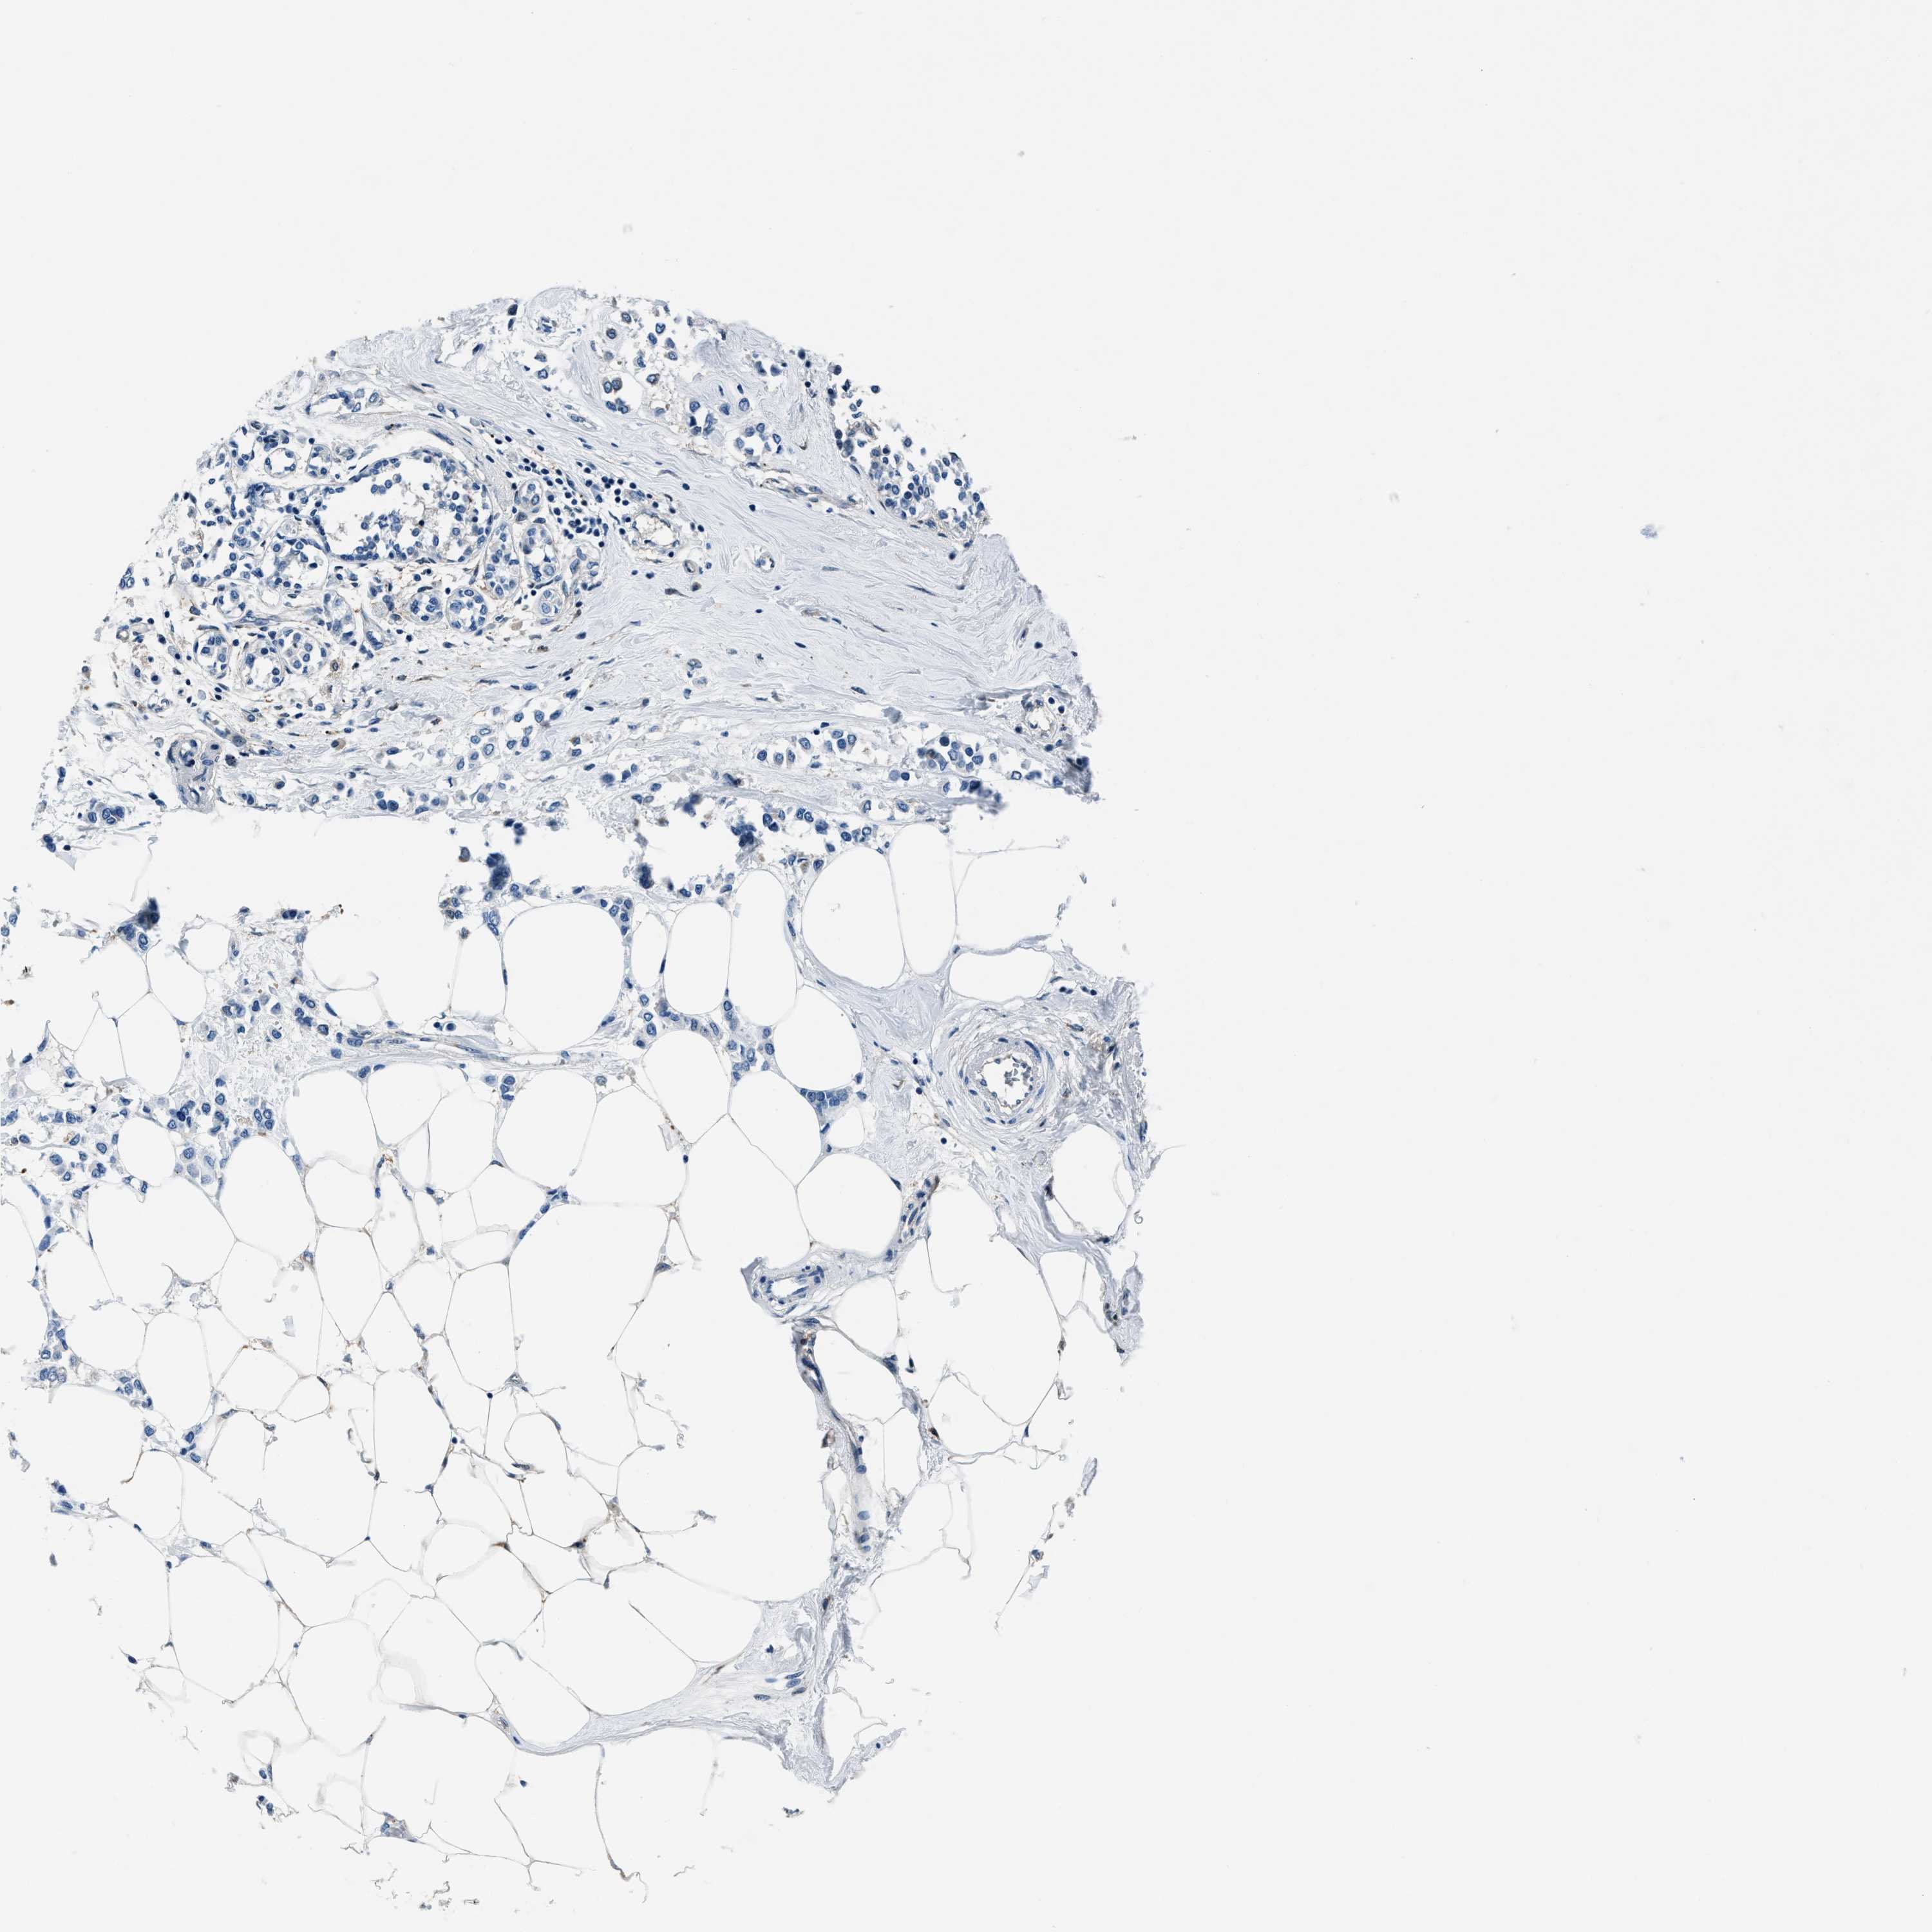

BRCA TCGA BRCA VALIDATION PROTEIN EXPRESSION